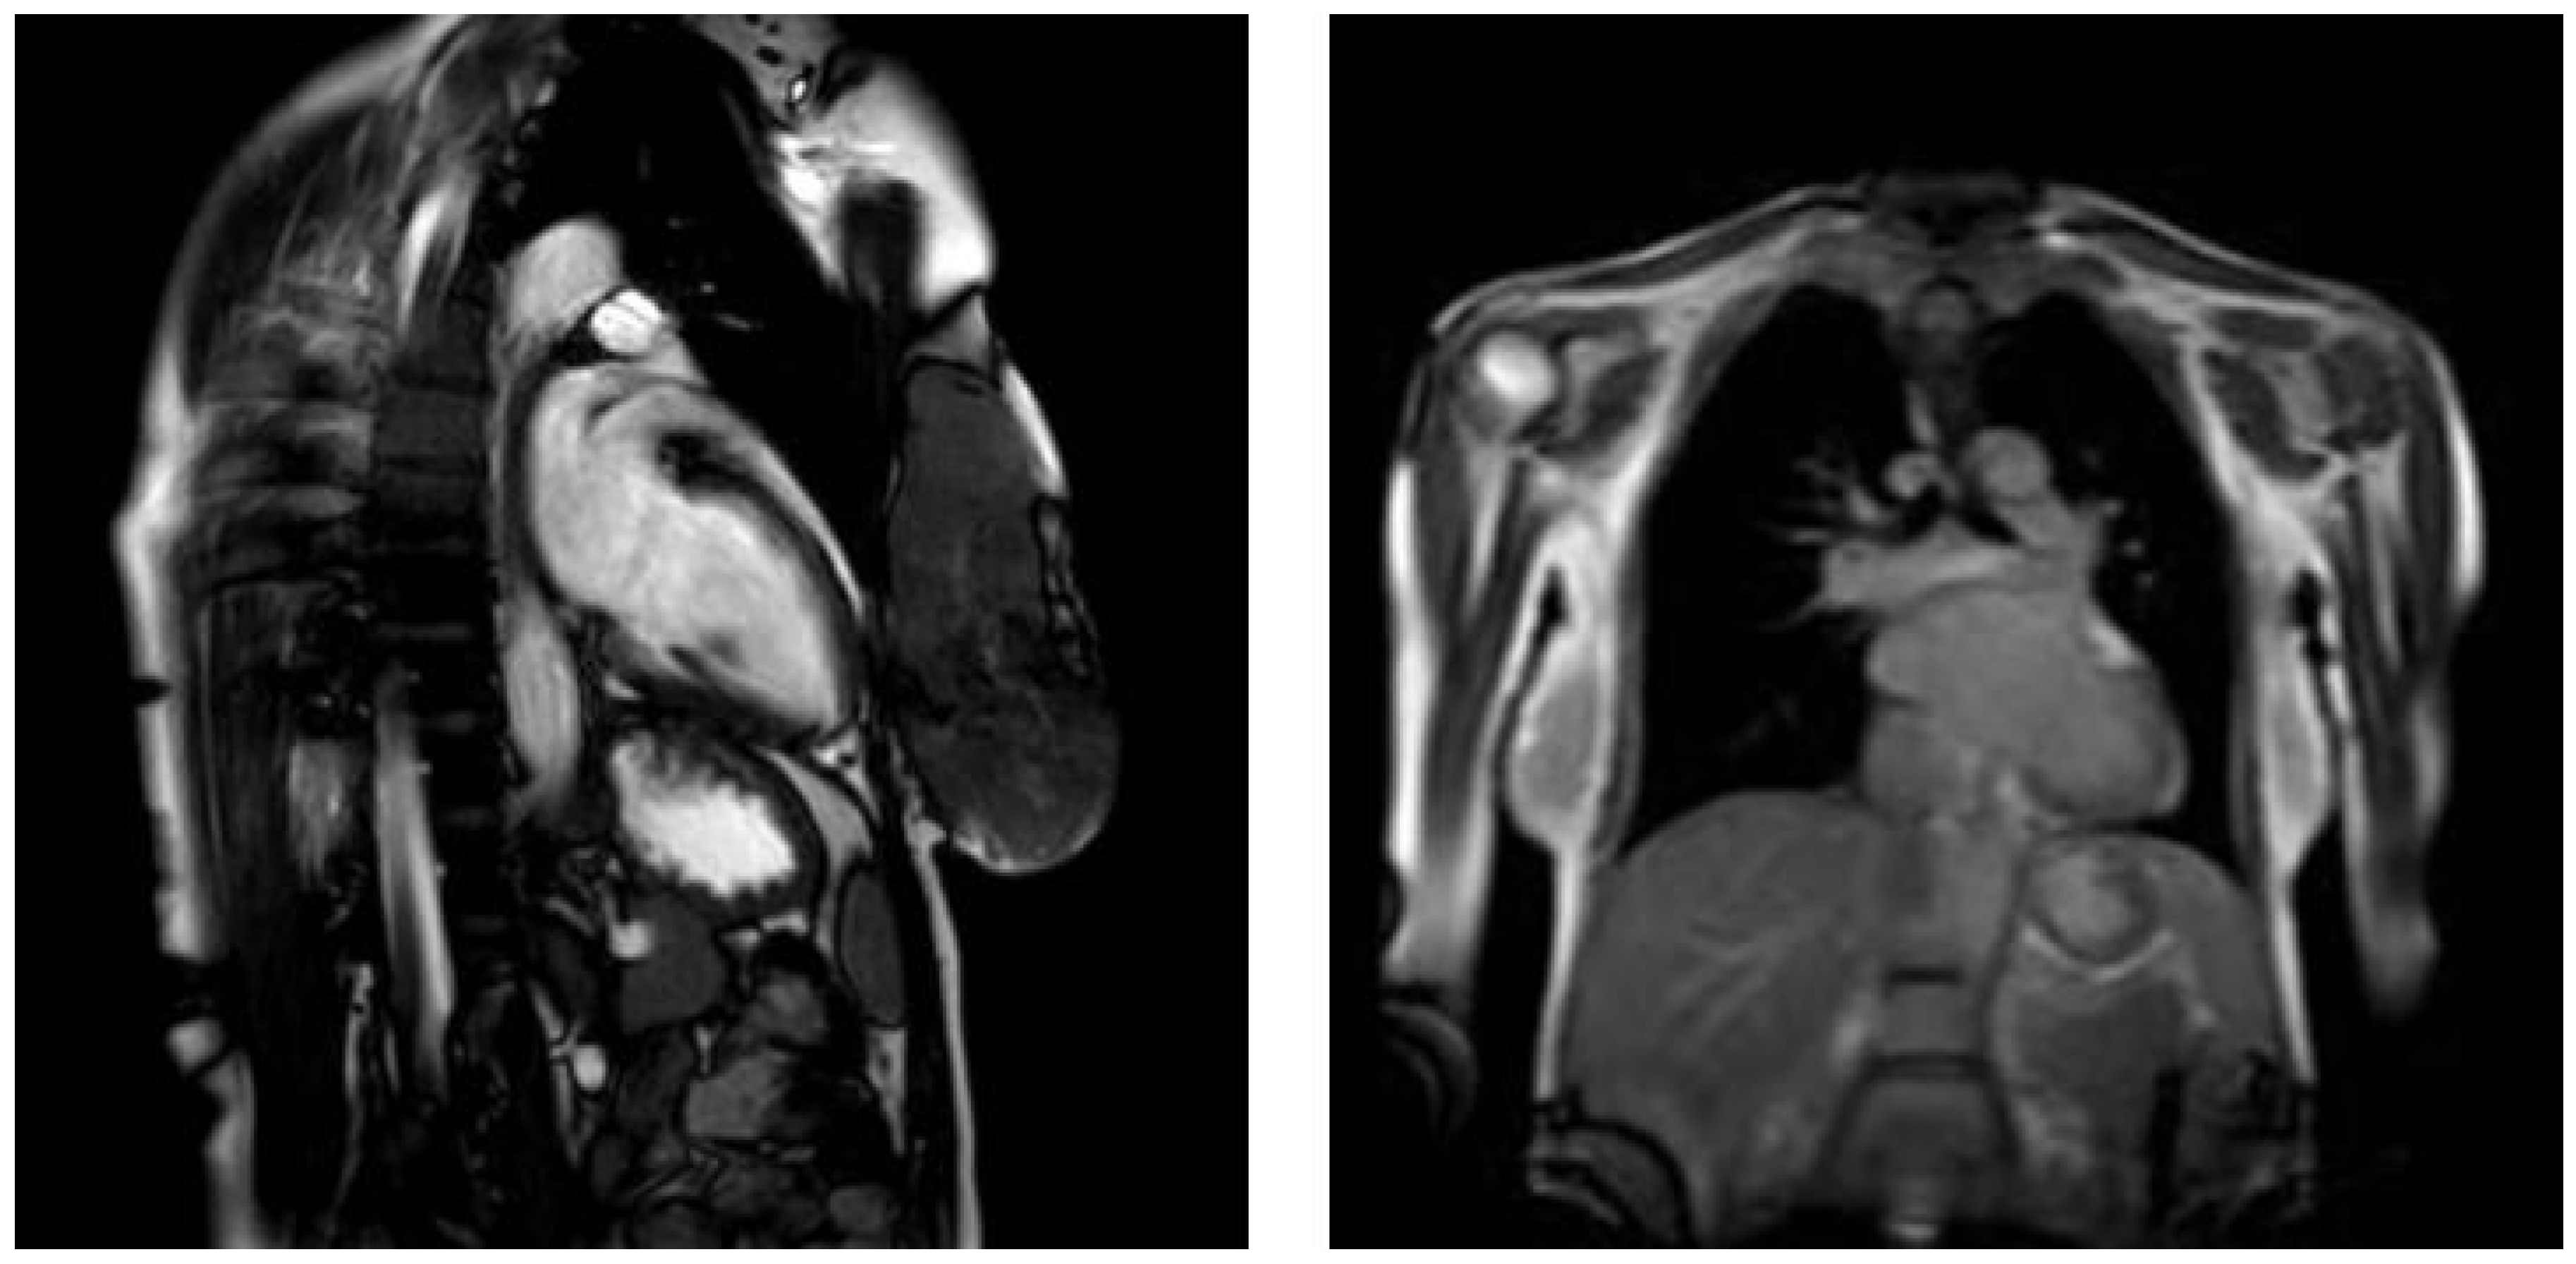

4. Case Presentation

| Cardiac magnetic resonance | Reduced LVEF, LV dilatation, LV hypertrophy, often oedema | Reduced LVEF, LV dilatation, oedema, hyperaemia, capillary leak, necrosis, and fibrosis |